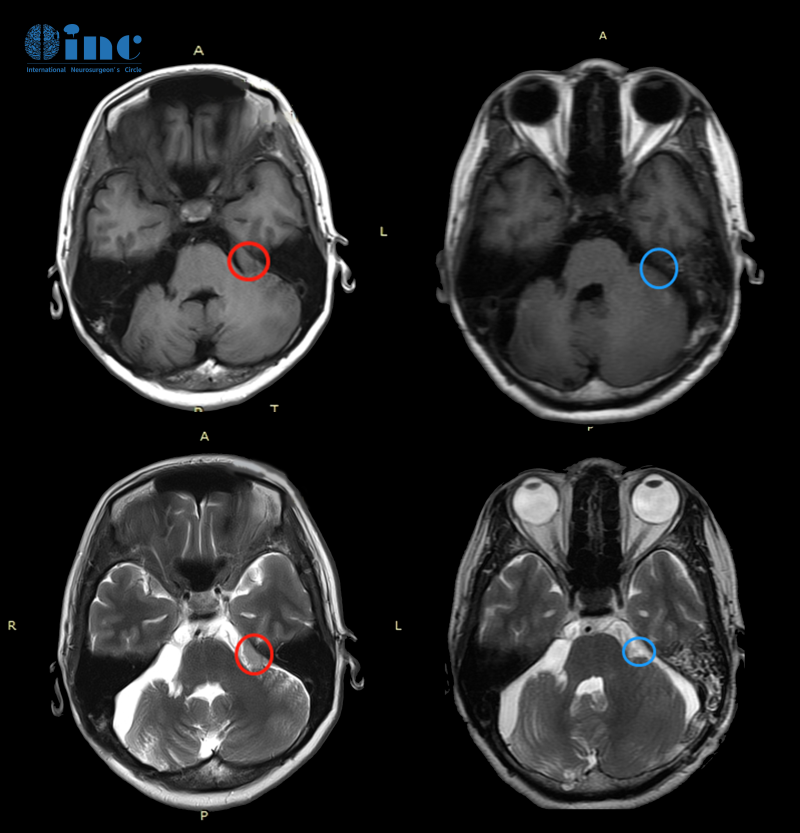

孟女士術前術后MR對比